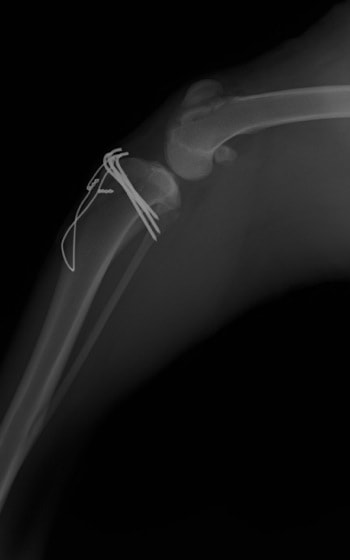

■ 症例20 ポメラニアン 8ヶ月 1.8kg

左右膝蓋骨脱臼 グレードⅢ

2ヶ月前から間欠的跛行が認められ、両膝の膝蓋骨脱臼整復術を行った。

手技は縫工筋及び内側広筋の解放、脛骨粗面の外側転位、滑車ブロック形造溝術、内外側関節包の縫縮を選択し実施した。

右側の膝蓋骨脱臼は上記手技で整復されたものの、左側はそれのみでは膝蓋骨が浮く様子が認められた。その為、PDS縫合糸にて膝蓋靱帯を1糸のみ縫合し、靱帯の縫縮を行った。